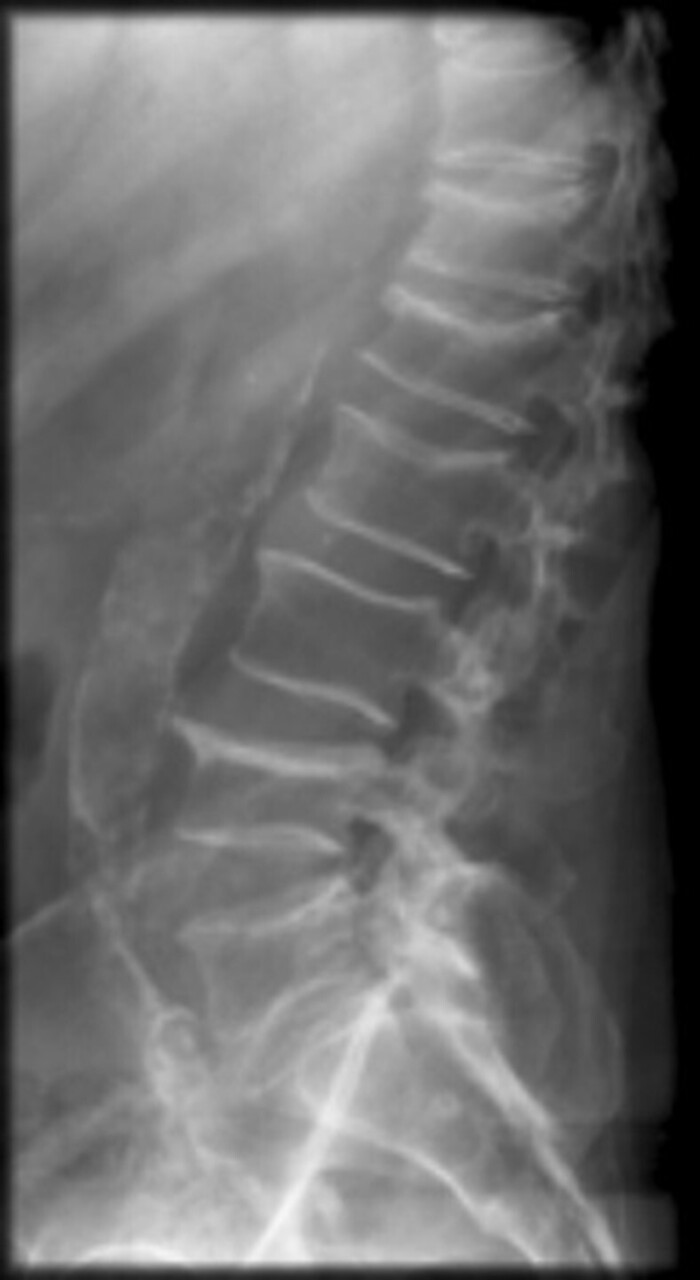

Vous réalisez en première intention une radiographie du rachis lombaire que voici.

Question 13 – Quel(s) élément(s) parmi les suivants est ou sont présent(s) sur cette radiographie ?

Visibles en T12, L1, L2, L4 (plateau supérieur).

Bien visible au coin antéro-supérieur de L4.

Il s’agit d’une question classique, savoir distinguer : tassement bénin ou malin, sans oublier les diagnostics différentiels infectieux (mal de Pott et spondylodiscite).

La localisation lombaire, les tassements étagés et les signes négatifs (repris ci-dessous) sont plutôt en faveur d’une ostéopathie déminéralisante.

L’absence de recul du mur postérieur, l’absence d’ostéolyse ou d’ostéocondensation sont peu en faveur d’une cause maligne.

L’absence d’ostéolyse en miroir, l’absence de pincement marqué de l’espace intervertébral sont peu en faveur d’une spondylodiscite.